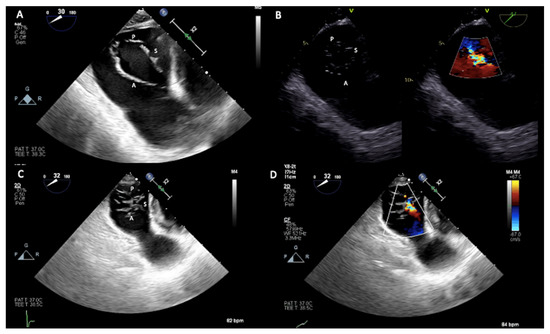

4.1. Two-Dimensional and Three-Dimensional Transthoracic and Transesophageal Echocardiography

4.2. Cardiac Computed Tomography and Cardiac Magnetic Resonance